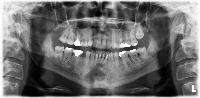

20231109_14 Computer Vision Project

Classes (34)

Apical Lesion

Apical lesion

Artifical crown

Calculus

Class 1 cavity filling

Class 2 cavity filling

Class 3 cavity filling

Class 4 cavity filling

Convergent root

Cystic lesion

Decidious teeth

Dilaserasgon

Distoangular Impacted tooth

Divergent root

Filling

Furcation lesion

Germ

Horizontal Impacted tooth

Horizontal bone loss

Implant

Lack of interproximal tooth contact

Mesioangular Impacted tooth

Microdontic tooth

Open margin

Overhang

Pontic

Post-Core Restorasyon

Pulp stone

Root fracture

Signs of caries

Signs of secondary caries

Vertical Impacted tooth

Yeterli canal filling

Yetersiz canal filling